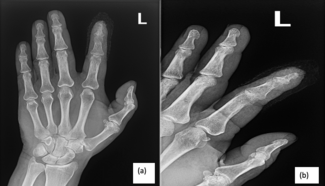

This retrospective review evaluates porcine acellular dermal xenograft interposition for failed trapeziometacarpal arthroplasty, demonstrating improved pain, function, and radiographic outcomes without complications.

Michael C. Doarn, MD; Mariel McLaughlin McArthur, MD; John J. Fernandez, MD